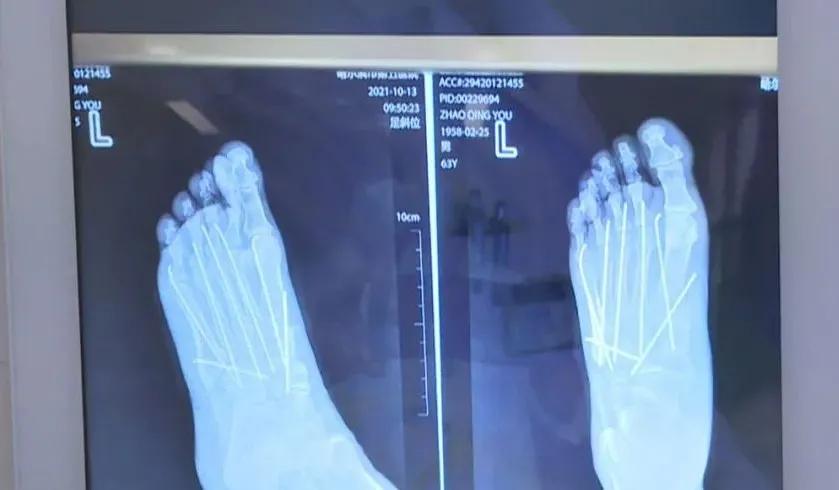

哈尔滨市第五医院骨二科主治医师 韩克城: 砸伤都是比较重的,整个脚趾从一到五都已经粉碎了,而且伴有脱位,而且楔骨也有骨折,整个中足脚面这一块都是骨折伴脱位的。砸伤以后,骨头折了以后,都会伴有软组织损伤,皮肤肿得很厉害。

从照片上可以看出,当时老罗的脚伤非常严重,左脚骨骼几乎全部骨折。到底是什么东西,威力这么大呢?

哈尔滨市第五医院骨二科主治医师 韩克城: 虽然五院现在有高端的机器人,但是传统的方法依然是很有效的,很经济实惠,七根钢针把五处骨折加上楔骨三处,达到一个满意的复位固定。